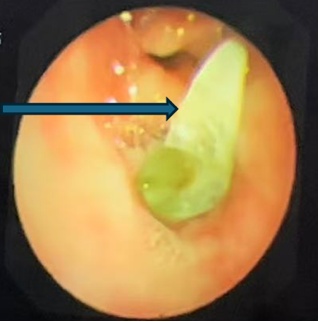

支气管镜检查显示右中间段支气管异物堵塞,镜下看似尖锐,表面大量黄绿色分泌物附着

最终用异物钳成功钳取出异物——

竟是一颗草莓味糖果的包装纸!

展开测量

长度接近3.5厘米